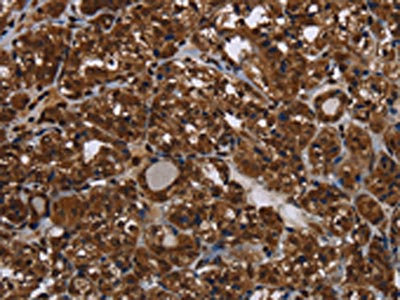

The image on the left is immunohistochemistry of paraffin-embedded Human ovarian cancer tissue using CSB-PA066115(HDAC7 Antibody) at dilution 1/20, on the right is treated with synthetic peptide. (Original magnification: ×200)

The image on the left is immunohistochemistry of paraffin-embedded Human thyroid cancer tissue using CSB-PA066115(HDAC7 Antibody) at dilution 1/20, on the right is treated with synthetic peptide. (Original magnification: ×200)